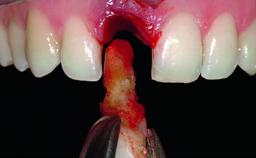

Replacement of a Compromised Upper Right Central Incisor: Hard- and Soft-tissue Augmentation, Late Placement of an RC Bone Level Implant

A 36-year-old male patient with a compromised maxillary central incisor was referred by his general dentist for consultation. The patient’s chief complaints were the gradual debonding of a temporary crown on the right central incisor and unsatisfactory esthetics due to an increasing diastema between the right central and lateral incisors. The patient reported a traumatic event some years previously, when a crown had been placed after root-canal treatment. The referring dentist wanted to provide a new crown restoration, but was concerned about the condition of the residual root. Anamnesis was negative for any other dental or periodontal pathology in the remaining dentition. The patient reported taking no medications: He was a smoker (10 to 15 cigs/day) and had realistic esthetic expectations.